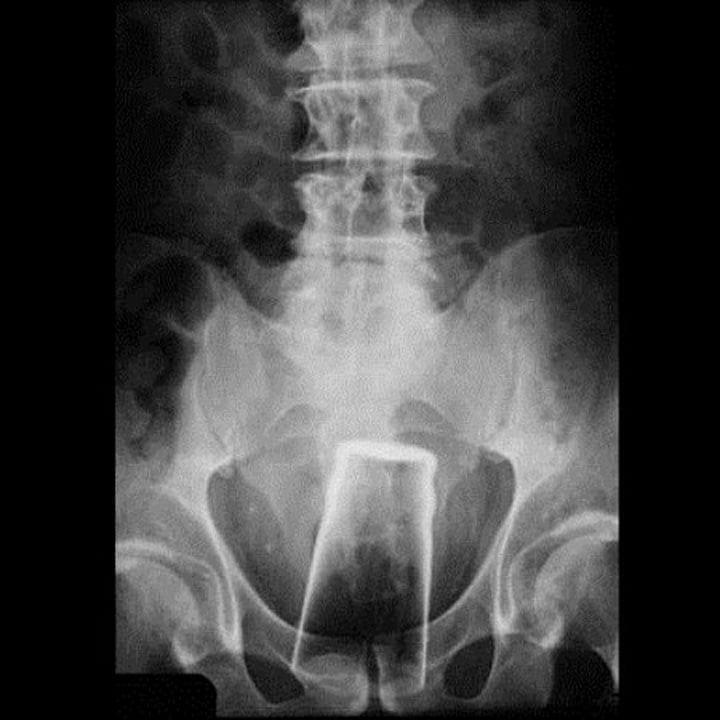

17. Как он умудрился засунуть туда стакан? Ума не приложу!